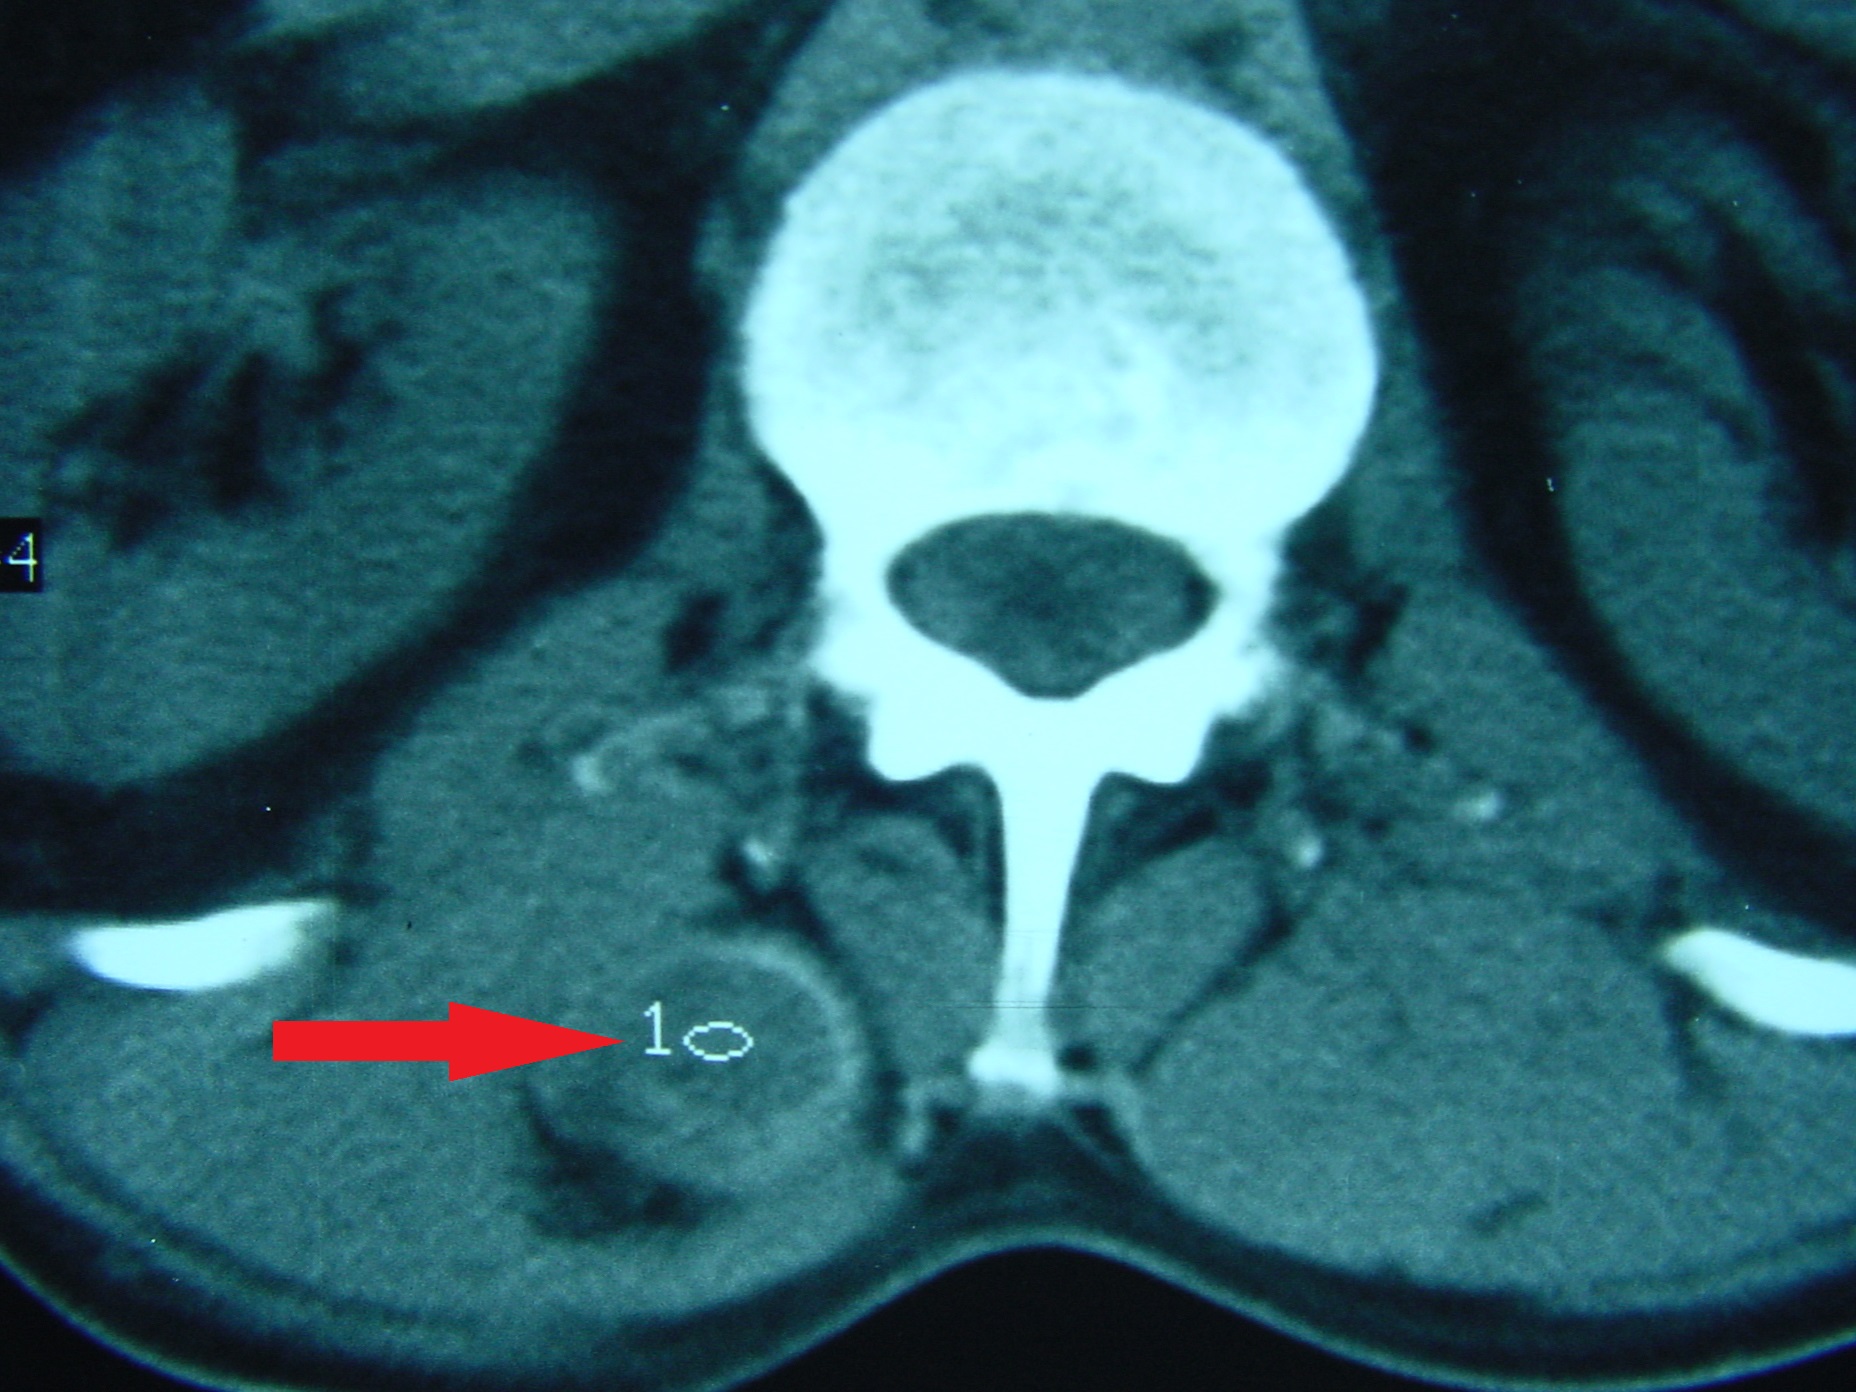

Εικόνα 2 α, β, γ, δ, ε, ζ. Αξονική τομογραφία – εγκάρσιες λήψεις.

Παρατηρείται η ύπαρξη κύστεων εντός των μαλακών μορίων (μυών) στην οσφυική μοίρα της Σπονδυλικής Στήλης.